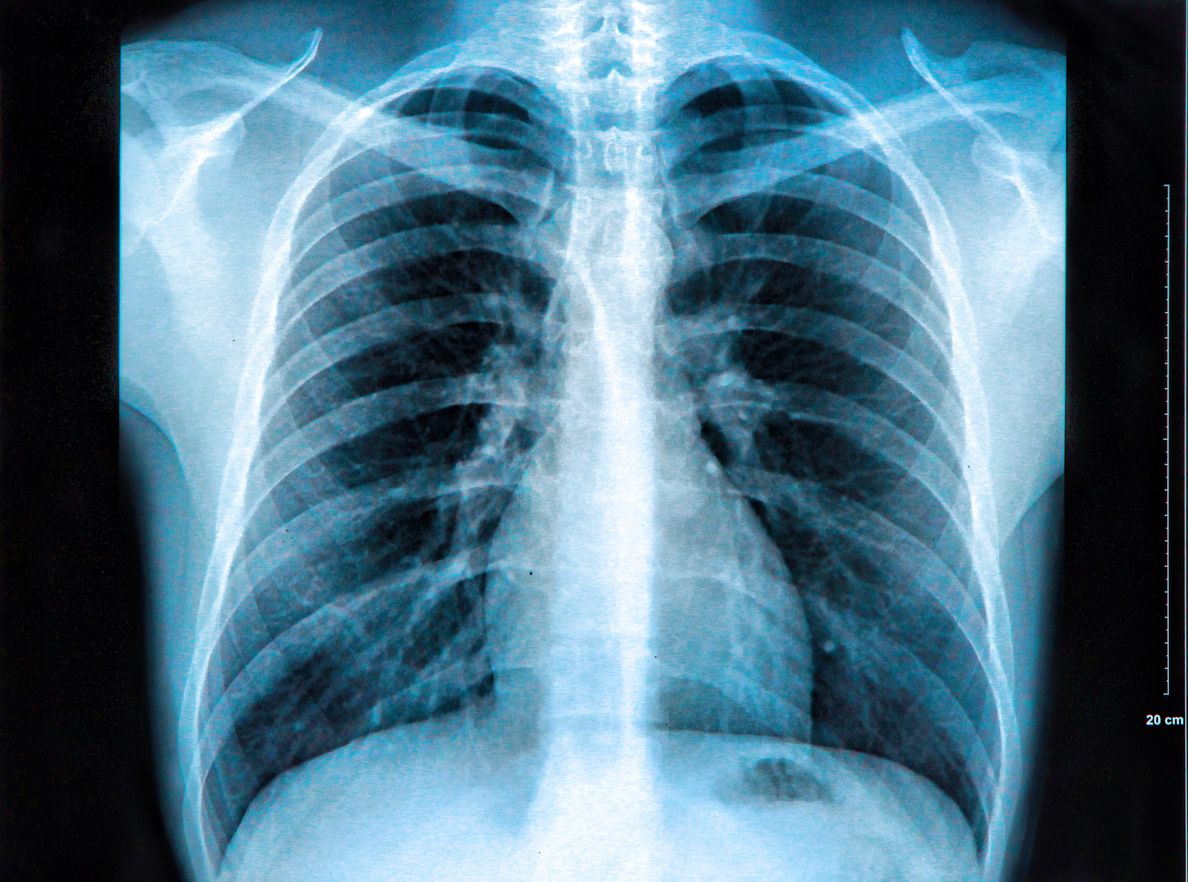

Wir alle sind uns der Gefahren des Rauchens bewusst. Es ist der größte Risikofaktor für Lungenkrebs. Tabakrauch enthält mehr als 60 verschiedene giftige Substanzen, die als krebserregend gelten. 25 Zigaretten pro Tag erhöhen das Risiko, an Lungenkrebs zu erkranken, um das 25-fache gegenüber Nichtrauchern. Das gilt nicht nur für Zigaretten, sondern auch Zigarren, Zigarillos, Pfeifentabak, Schnupftabak, Kautabak und Cannabis (insbesondere, wenn es mit Tabak gemischt wird). Wer also nicht raucht, bekommt keinen Lungenkrebs – ist es so einfach?

Leider nicht. Denn auch Nichtraucher können an Lungenkrebs erkranken – auch, wenn dies seltener auftritt. Sogar Menschen, die in ihrem Leben gar nie geraucht haben oder die dem Glimmstängel schon lange abgeschworen haben. Aber es gibt einen Unterschied: Lungenkrebs von Nichtrauchern weist gänzlich andere molekulare und biologische Merkmale auf und spricht anders auf Behandlungen an als Raucher-Lungenkrebs. Laut den Onkologen von Yale Medicine können die Betroffenen auch von anderen Symptomen betroffen sein. Anne Chiang, medizinische Thoraxonkologin am Smilow Cancer Hospital in Yale, erklärte: "Früher dachten wir, dass alle Lungenkarzinome gleich sind, aber jetzt wissen wir, dass es verschiedene Arten gibt. Die gute Nachricht ist, dass die Arten von Lungenkrebs, zu denen Nichtraucher neigen, in der Regel auf einer molekularen Veränderung oder Mutation beruhen, die im Tumor nachgewiesen werden kann, und dass es für sie Medikamente und Therapien gibt."

Nichtraucher und Raucher bekommen unterschiedliche Krebsarten

Bei den meisten Nichtrauchern wird ein nicht-kleinzelliges Karzinom, das sogenannte Adenokarzinom, diagnostiziert, das oft in den äußeren Bereichen der Lunge beginnt, in den schleimproduzierenden Zellen, die die kleinen Atemwege, die Bronchiolen, auskleiden.Im Gegensatz dazu neigen Raucher dazu, eine Art von nicht-kleinzelligem Lungenkrebs, das Plattenepithelkarzinom, zu entwickeln, so die Yale Onkologen.

Thoraxchirurg Daniel Boffa erklärt es bildhaft: "Das Adenokarzinom hat eine andere Form als andere Arten von Lungenkrebs. Wenn Sie Raucher sind, können Sie sich Ihre Lunge als einen Beutel mit weißen Murmeln vorstellen, und Krebs ist, als ob man eine schwarze Murmel hineinlegt", erklärte er. "Die Art von Krebs, die ein Nichtraucher bekommt, ist eher so, als würde man schwarzen Sand hineintragen. Statt eines Flecks oder Klumpens ist es eher ein unscharfes Gebiet. Er ist eher diffus. Und bei Nichtrauchern tendiert der Krebs dazu, langsamer zu wachsen."